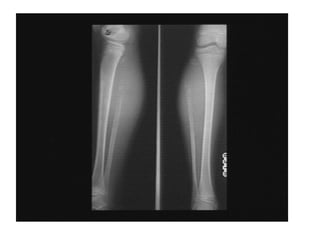

Rickets

• Rickets is the softening and

weakening of bones in children,

usually because of an extreme and

prolonged vitamin D deficiency.

• Some skeletal deformities caused by

rickets may need corrective

surgery.